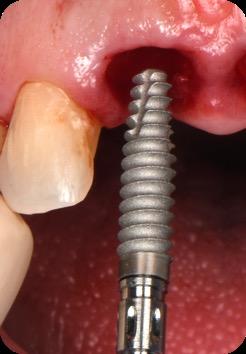

BioHorizons has introduced a new implant system that combines the advanced thread design of the Tapered Pro with the precision and stability of the Conelog conical connection. This integration delivers enhanced surgical handling, improved primary stability, and long-term biological benefits, supporting better patient outcomes in both aesthetic and functional zones.

This case was performed by Dr Homa Zadeh, DDS, PhD, a respected leader in periodontology and implant dentistry. Dr Zadeh’s approach emphasizes biologically driven protocols and evidence-based techniques, making this case a strong example of clinical excellence using the Tapered Pro Conical system. It involves the replacement of two front anterior teeth after they fractured off and the full restoration process.

Fig 5. Central incisors extracted using minimally invasive protocol. Alveolar bone and gingival tissues were intact after extraction

Fig 6. BioHorizons Tapered Pro Conical implants of 3.8 x 15mm placed according to the plan.

Fig 7. Implants immediately after installation.